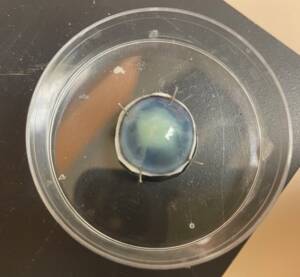

Mimicking a superficial ulcer by scoring and removing the epithelium and anterior stroma of the canine cornea. Fluorescein staining was used to confirm the presence of the superficial ulcer.

Canine cornea inoculated superficially on the ulcer bed with live Pseudomonas aeruginosa bacteria.

Storage of inoculated cornea and control in the incubator for 24 hours. The corneas are immersed in a storage solution to prevent desiccation. The image shows an inoculated cornea with live bacteria.

Treatment of the inoculated cornea with UV-C for 15 seconds at a distance of 10 mm.